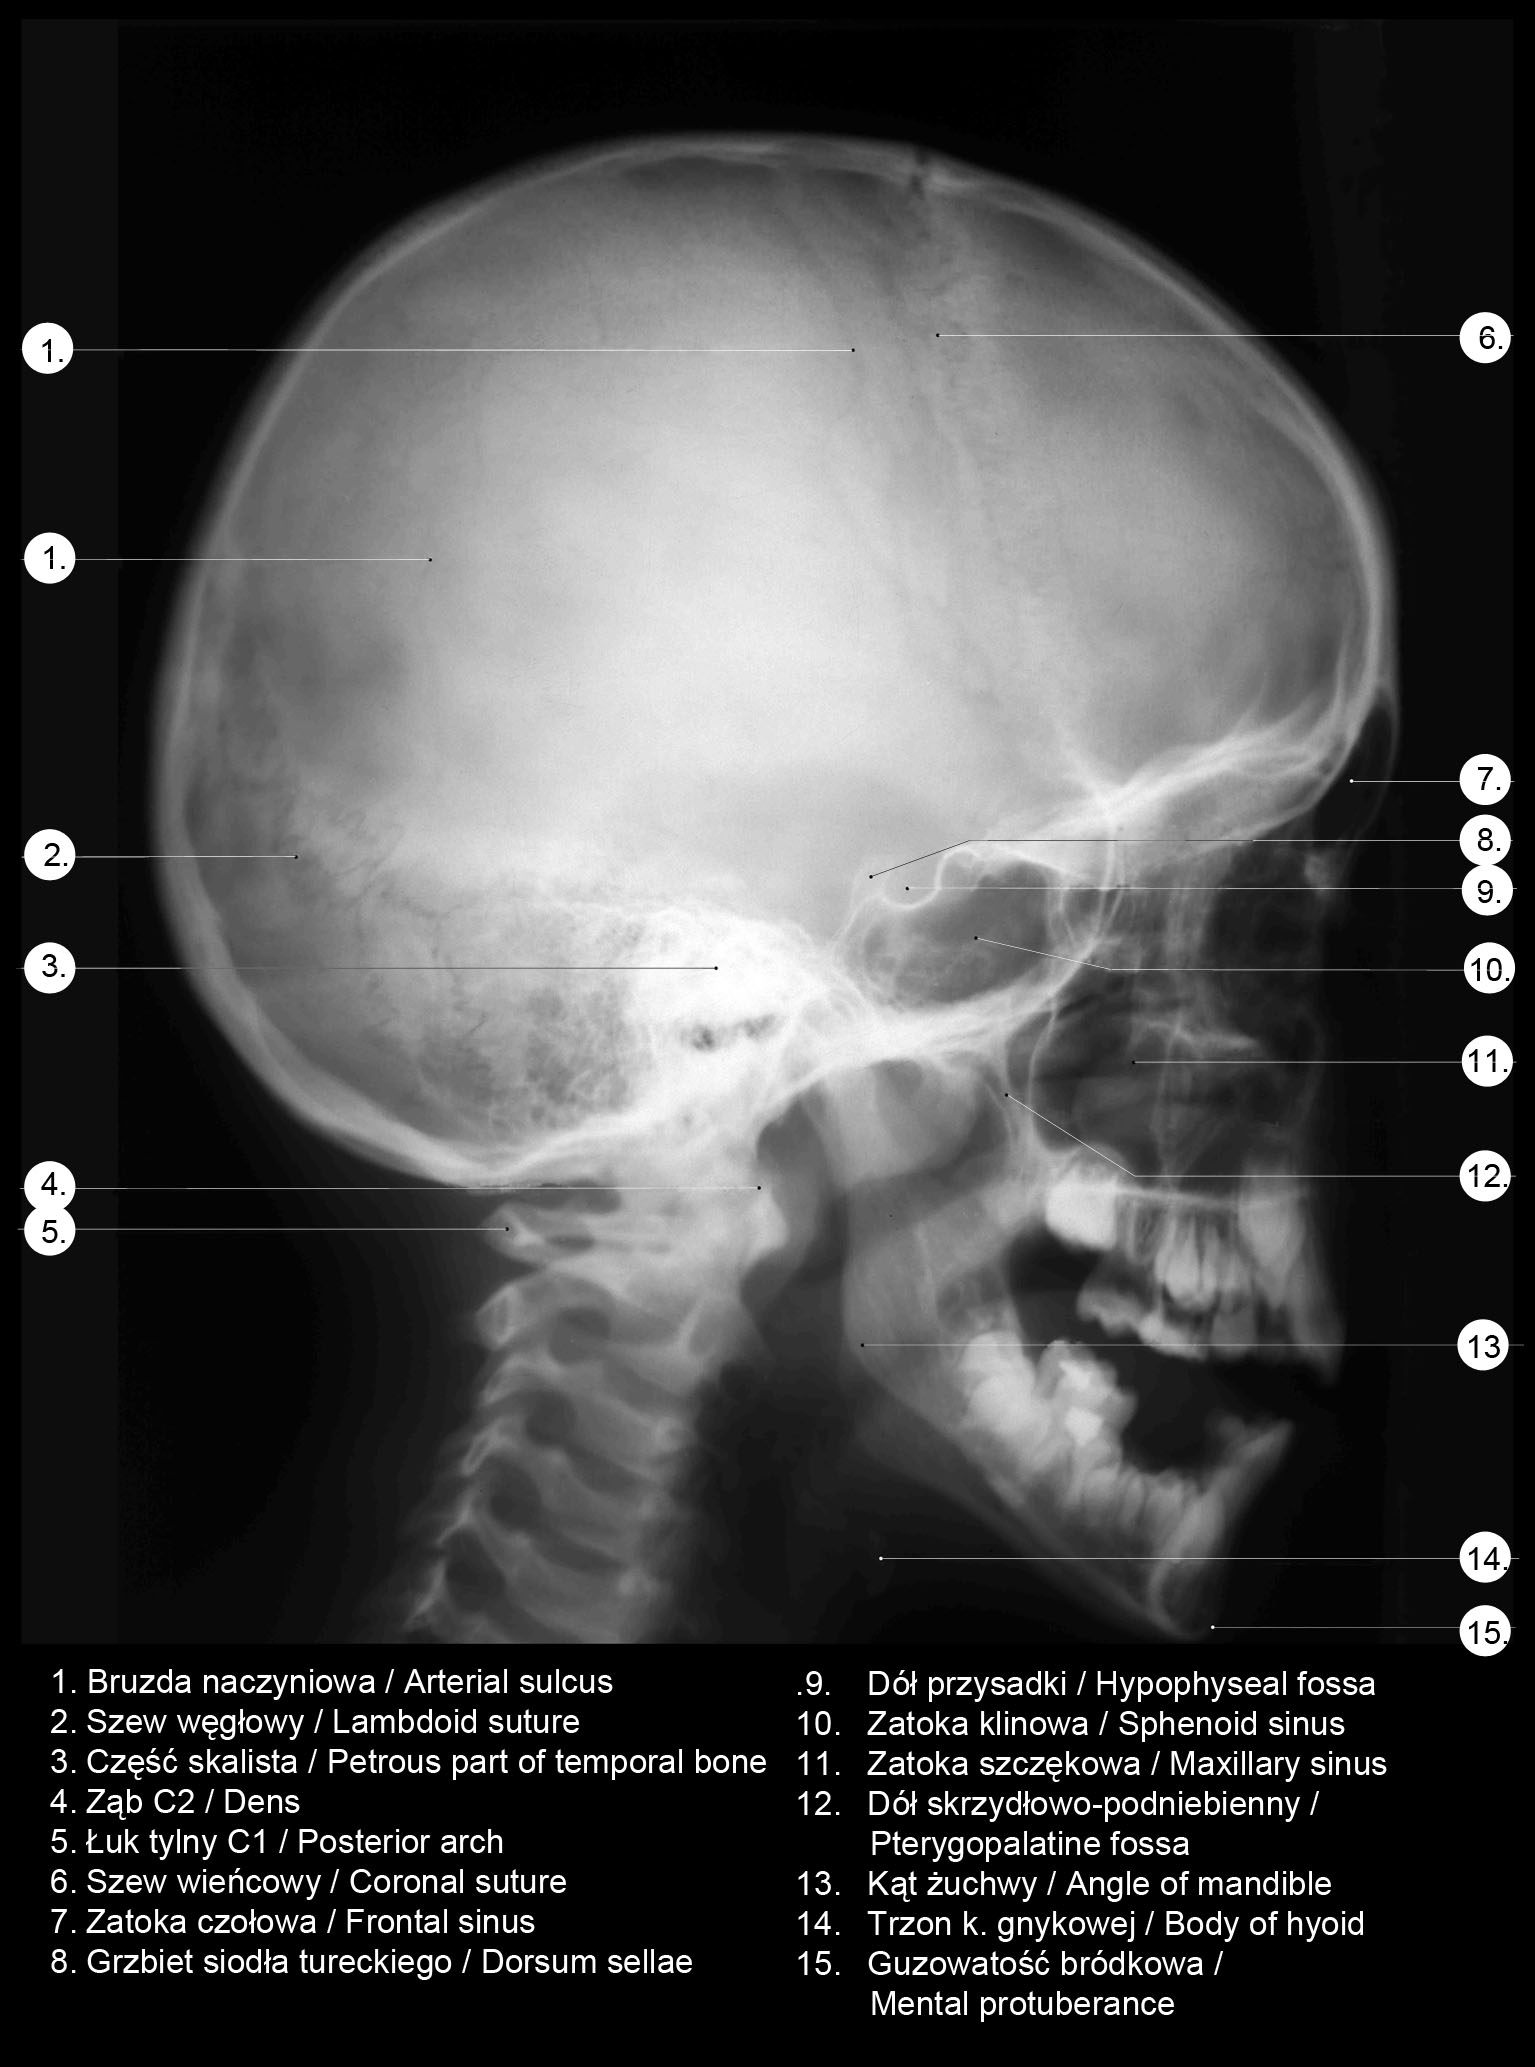

RTG głowy frontalny.

RTG głowy boczny.

RTG głowy od góry.

. RTG głowy człowieka.